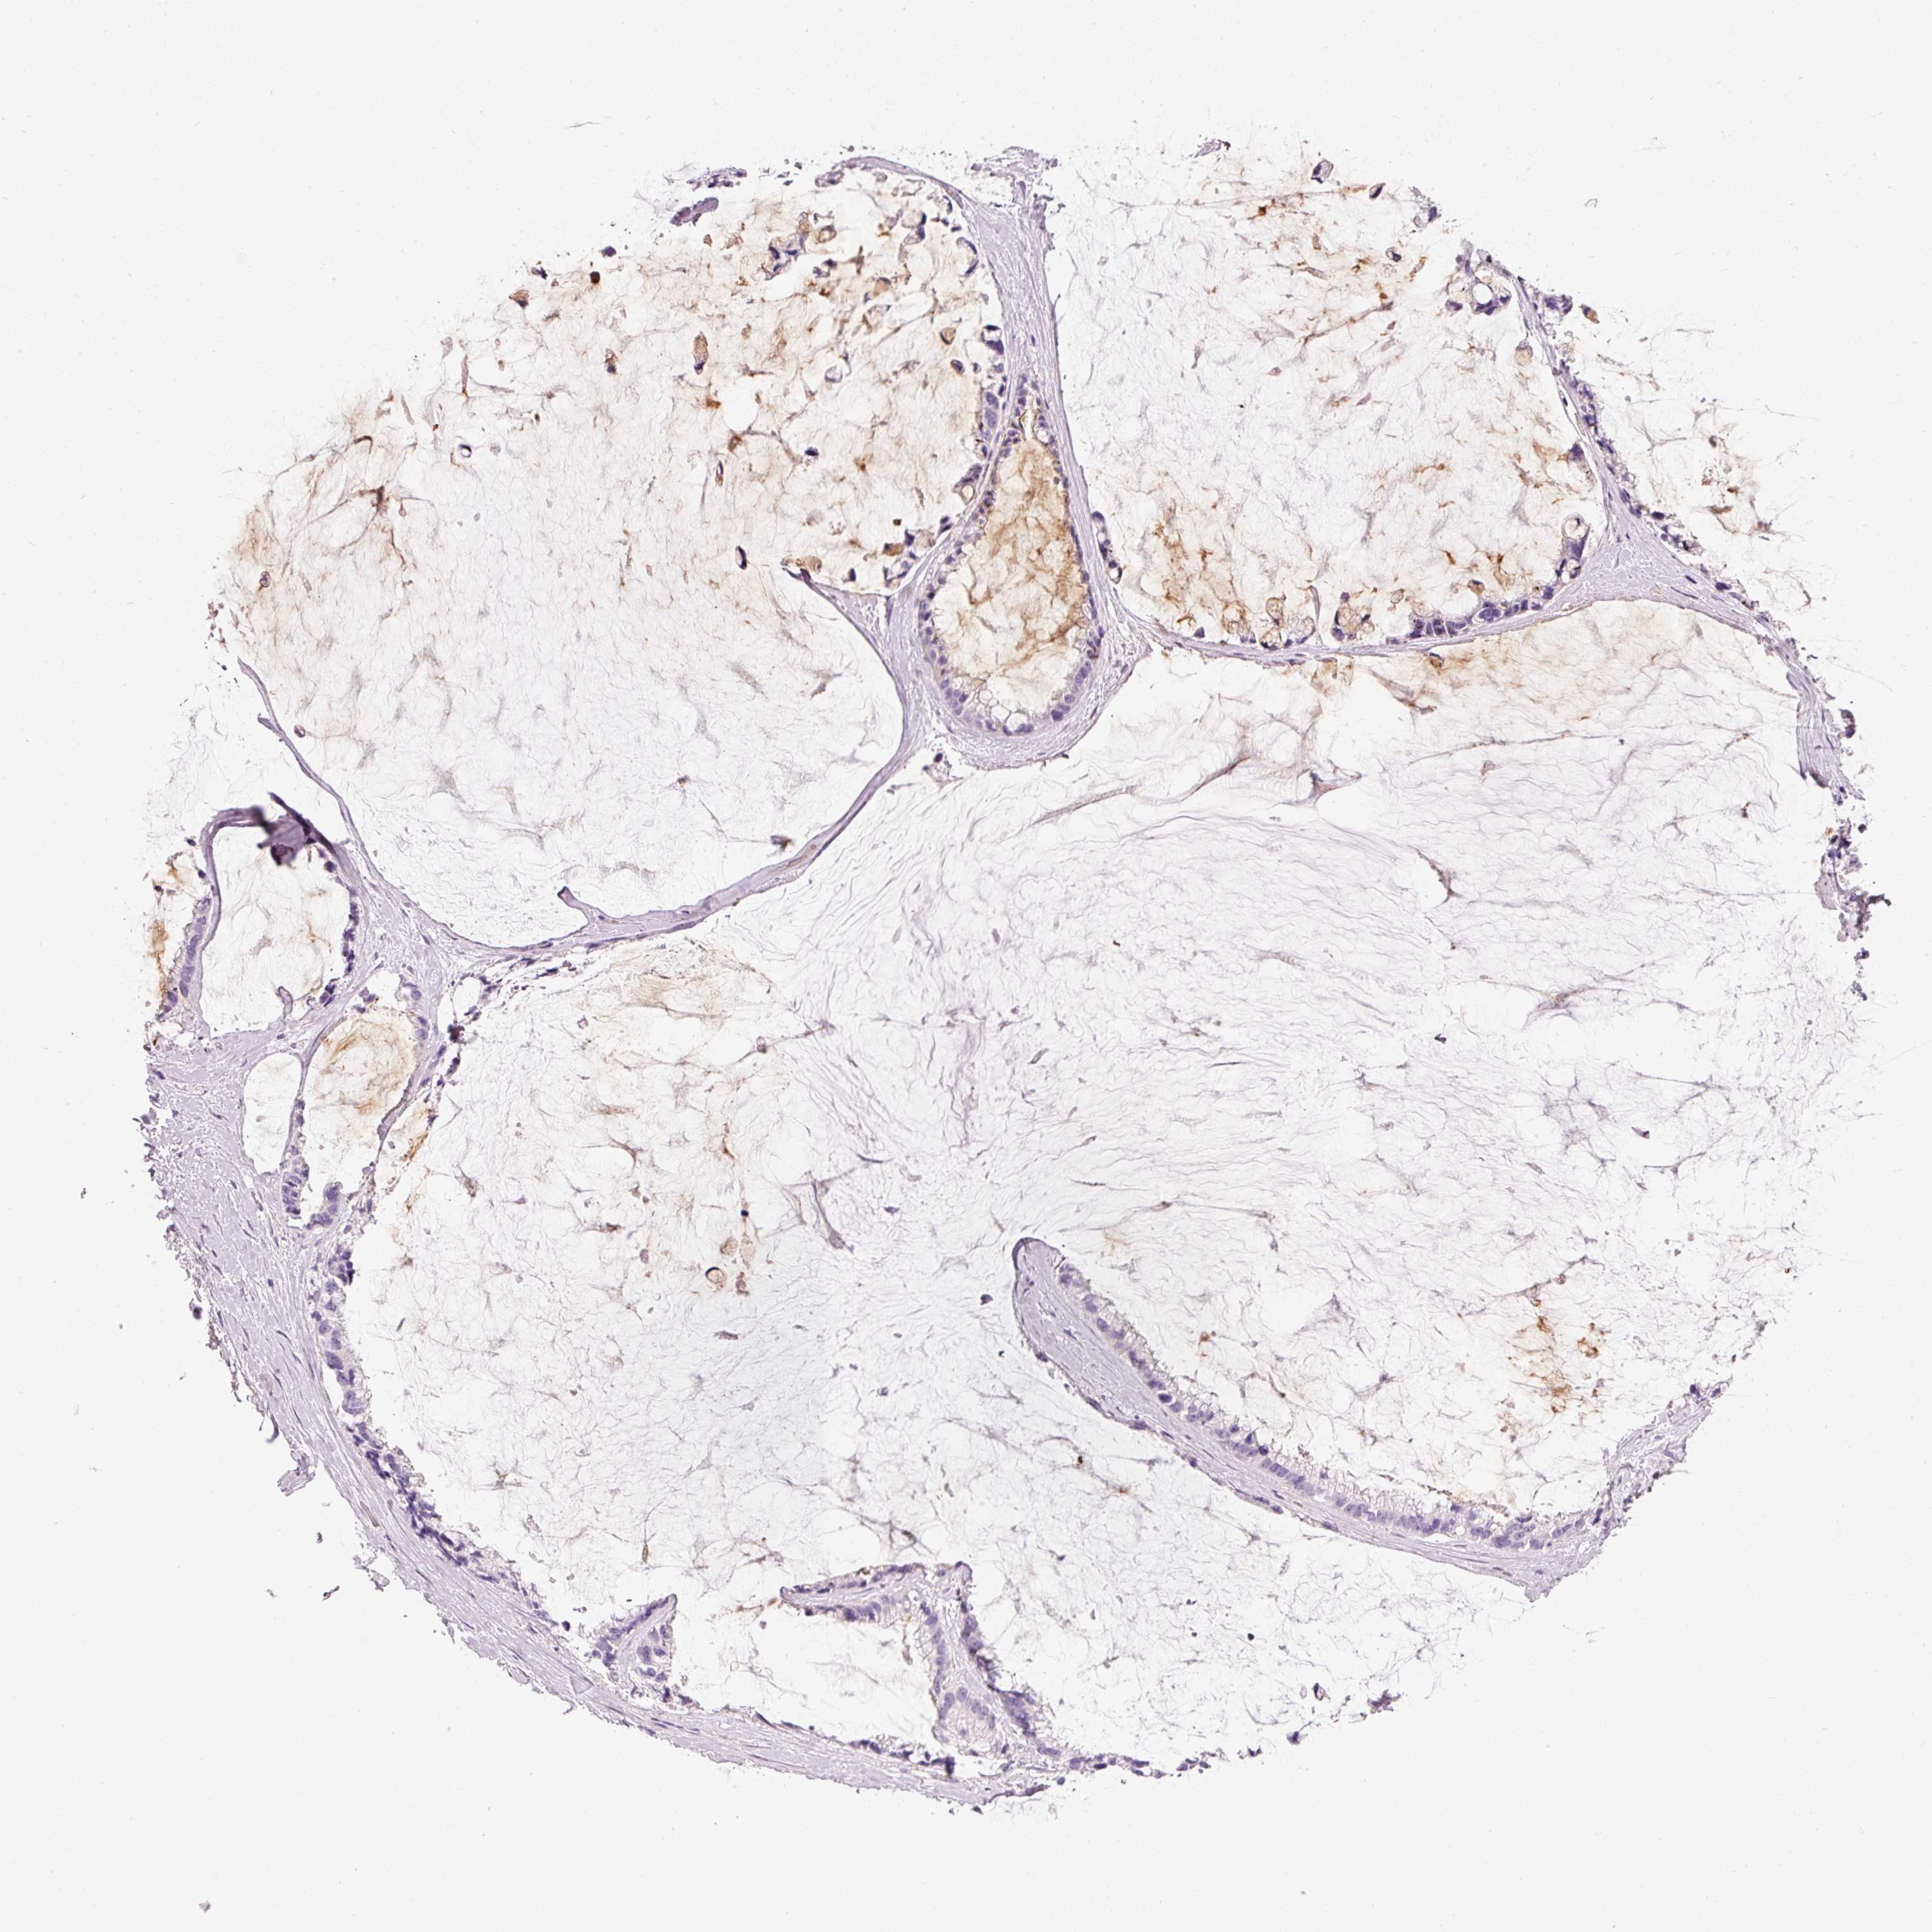

OVARIAN CANCER - Protein expressioni

A mouse-over function shows sample information and annotation data. Click on an image to view it in a full screen mode. Samples can be filtered based on level of antibody staining by selecting one or several of the following categories: high, medium, low and not detected. The assay and annotation is described here.

Note that samples used for immunohistochemistry by the Human Protein Atlas do not correspond to samples in the TCGA dataset.

Antibody stainingi

Antibody staining in the annotated cell types in the current human tissue is reported as not detected, low, medium, or high, based on conventional immunohistochemistry profiling in selected tissues. This score is based on the combination of the staining intensity and fraction of stained cells.

Each image is clickable and will lead to virtual microscopy that enables deeper exploration of all samples and also displays staining intensity scores, fraction scores and subcellular localization as well as patient and tissue information for each sample.

HPA040615

Cystadenocarcinoma, serous, NOS

Carcinoma, endometroid

Cystadenocarcinoma, mucinous, NOS

Carcinoma, NOS